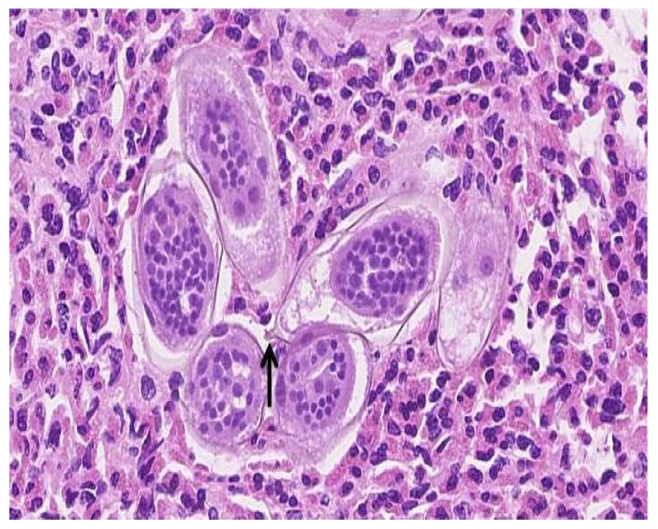

The urinalysis demonstrated a mild increase in the 21–50 red blood cells (20–50/HPF) and white blood cells (11–20 white blood cells/HPF). The urine cytology did not reveal any tumor cells, and the microscopic examination of the urine did not demonstrate any ova or parasites. Nitrites were not observed, and no growth was observed in the urine culture. The complete blood count revealed a white blood cell count of 5.7 × 109/L (range 4.5–11 × 109/L), hemoglobin 132 g/L (range 120–160 g/L), and platelets 381 × 109/L (range 140–440 × 109/L). The differential white blood cell count was normal, except for mild eosinophilia, with 1.15 × 109/L (range 0.0–0.4 × 109/L), or 18.0% (range 0.0–5.0%). The blood chemistry levels were all within normal ranges. A computerized axial tomographic scan (CT) of the abdomen and pelvis was performed and showed no pathologically enlarged lymph nodes. However, it revealed a 1.5 by 1.5 by 0.9 cm pedunculated intraluminal urinary bladder mass on the right side. The interpreting radiologist suggested that the mass could be better assessed by an ultrasound, which is shown in Figure 1. Although the ultrasound showed no stone, it raised concerns regarding possible bladder neoplasia. The patient underwent a cystoscopy with a transurethral resection of the mass for a histological assessment. The microscopic examination, as shown in Figure 2, revealed organisms that were morphologically compatible with the eggs of S. haematobium. We prescribed the patient 1200 mg of praziquantel orally every 12 h for one day (two doses). The one-month post-treatment follow-up included monitoring for eosinophilia and a microscopic examination of the urine (S. haematobium), which revealed a normal reading that confirmed that the patient had been cured.

Figure 2.

High magnification (approximately 40×) of a hematoxylin and eosin-stained section of the large bladder lesion resected transurethrally. Numerous elongated Schistosoma spp. ova with viable miracidia in the background of many eosinophils are identified. A terminal spine (arrow) is present on one of the eggs, which confirms that S. haematobium is the responsible pathogen.